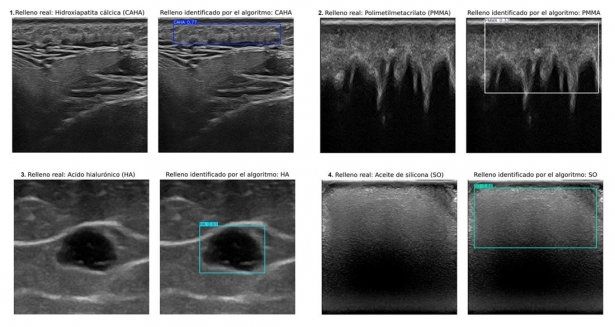

El sistema automatiza el diagnóstico en tratamientos cosméticos, mejorando la precisión y facilitando la atención clínica